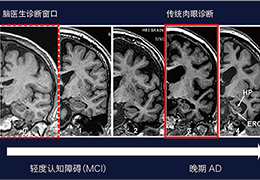

Everyone – including surgeons, patients and their loved ones – benefits from being better informed by the wealth of information buried within CT and MRI scans. Pro Surgical 3D gives surgeons more information to develop optimal treatment plans for patients. It also helps patients and their support group better understand their medical condition and proposed treatment options.

Better understanding of a condition, disease or diagnosis

Ability to clearly see the condition or disease

Better grasp of treatment progress by comparing scans over time

Side-by-side comparative assessment for pre- and post-operative scans.